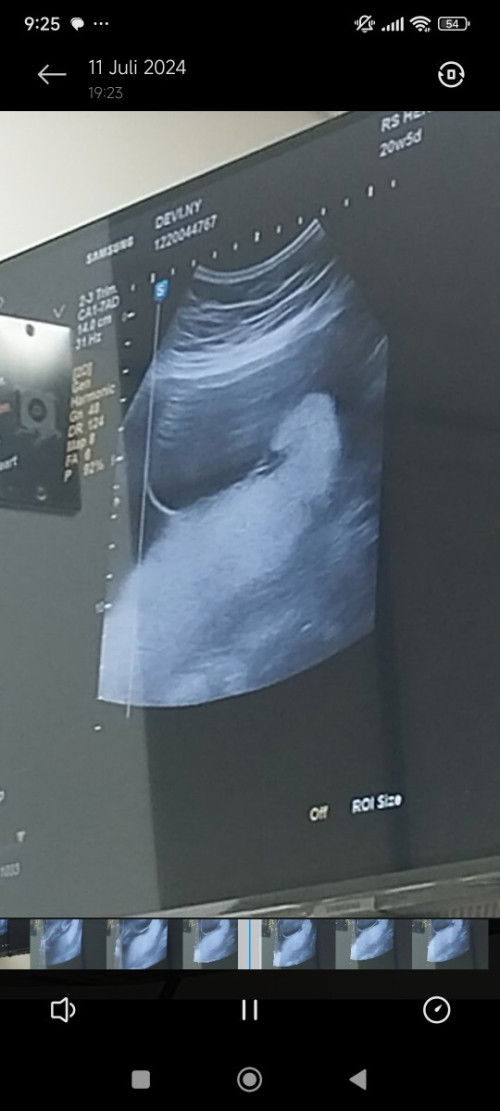

Di duga spina bifida bagi pengalaman nya bun 🥺 saya jadi ovt.

Kemarin malam saya USG ke dokter obgyn di salah satu RS, bulan kmrn ada lingkaran di bagian bawah baby diameter 2cm dan di jadwalkan bulan ini untuk kontrol lagi, dan ternyata lingkaran putih itu semakin besar skrng 7cm. Perkiraan dokter itu spina bifida atau kista. Nanti di tanggal 20 saya di rujuk ke RS Sarjito untuk cek kembali dan memastikan kembali bun. Bunda disini ada yg punya pengalaman serupa? Bingung bun 😭

Kepikiran banget 😭

Bunda aku habis usg kehamilan 15 minggu di bagian pantat babynya kyk ada gumpalan baru besok ke dokter fetomaternal. Sharing dong bunda ada yg pernah ngalamin?